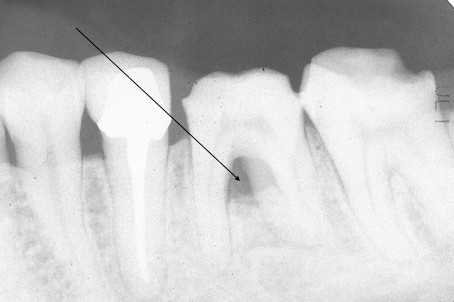

近未来の根管治療法2.6

9歳男子、右下E 、Per+ 右下6、隣接面カリエス、咬合性外傷Perというのは虫歯から歯髄に細菌が入って腫れたりすることで、日本語では根尖性歯髄炎という。よくあるケースではあるのだが、最近はあまり見ないので、画像をアップしておきたい。隣接面カリエスの成因についてはどこかで解説したような気がするが、記事は失われてしまったかもしれない。これか?この時はまだ水素イオンの流れは登場していない。https://plaza.rakuten.co.jp/mabo400dc/diary/201203300001/「虫歯の電気化学説」的には要因はいくつか考えられ、1、咬合性外傷による微細なクラックや応力腐食割れ部分が他の健全歯質部分よりイオン化傾向が高い腐食電極になる。2、2つの歯に挟まれた狭い空間なので、酸素濃度が低く酸素濃淡電池のマイナス極(腐食電極)になる。3、同様に狭い空間に細菌が繁殖すると酸素濃度が低くなるだけではなく、酸性環境になりやすい。4、2つの歯が近接もしくは接触しているので、この部分にイオン伝導が集中しやすい。などがある。初診時の顔は腫れており、小児科に行くと抗生剤の点滴を受け、このまま入院が必要になるかも?と脅かされたそうだ。とりあえず歯医者に行け!と言われて、来られた。確かに抗生物質のない時代、昭和30年代以前はPerから蜂窩織炎や菌血症、敗血症で命を落とす人は多かった。最近は抗生物質の効かない細菌も増えてきているようで、まだ1症例しか遭遇していないが、その場合は入院して抗生物質以外の消毒薬で洗浄を繰り返すしかない。幸いこの子の場合はそうではなかった。レントゲン写真ではEの遠心の虫歯は歯髄と交通しているように見える。この部分から細菌感染したのだろう。6の近心にも小さな虫歯が見える。冠部歯髄の上にある天蓋を除去する過程は歯科医師以外は見ることが難しいと思うので供覧したい。近心根の髄角部分からは出血している。まだ歯髄が生きている可能性があるか、5番の歯嚢部分から出血しているのかもしれない。近心根はその場で根管を超音波洗浄して抗菌剤添加α-TCP+α-TCPセメントの二重仮封で根管充填した。遠心根は感染による炎症がひどいかもしれないと思って根管充填は1週間待つことにしてオープンにした。エンドチップで触った感じでは、それほどひどい感じは受けなかったので、近くの子なら根菅充填してしまうところだが、遠方なので、抗生物質投与で経過を見ることにした。で、1週間後。まず6番の隣接面カリエスの処置をすることにした。この矢印部分の噴火口状の部分はイオン(水素イオン)が通り抜けた部分で、もっとも虫歯の進行している部分だ。水素イオンが何らかの起電力に引かれて、歯から飛び出す時に歯のカルシウムから電子を奪ってカルシウムイオンとなって溶出し、歯質のハイドロキシアパタイトの結晶構造が壊れるのが虫歯だからだ。このように特に硬組織の病変に関しては電気化学的な視座がないと全く理解できない。早く歯科業界は追いついてもらいたいものだ。遠心根も2根あったが、超音波洗浄してα-TCPセメントで根菅充填してCRで歯冠を再建して終わった。超音波洗浄時に出血が見られたが、そのまま根充している。